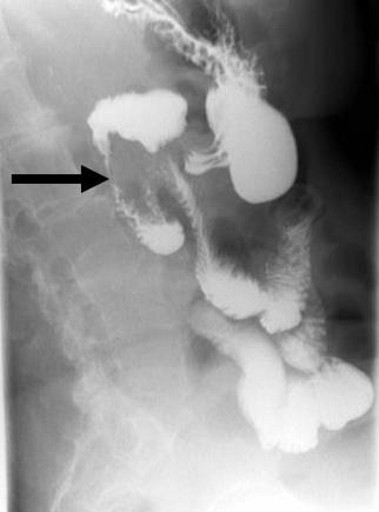

A 72-year-old female presented with acute epigastric pain radiating to her back, associated with nausea and vomiting. There was no associated hematemesis, jaundice or fever. The following illnesses were of note in her medical history: a cholecystectomy (for biliary colic attacks), hypertension and osteoarthritis. She was taking 100 mg/day of atenolol and 2 g/day of paracetamol. She abstained from all alcohol consumption. On examination, she appeared to be in pain and was dehydrated. Her abdomen was supple with epigastric tenderness. Laboratory examination revealed leukocytosis (11,500 mm-3; reference range: 4,000-10,000 mm-3). Pancreatic enzymes were abnormally increased (lipase: 956 IU/L, reference range: 114-286 IU/L; amylase: 765 IU/L, reference range: 25-115 IU/L). Hepatic enzymes, calcemia and triglyceridemia were all within the normal range and there was no biological cholestasis. An abdominal CT-scan confirmed the diagnosis of acute pancreatitis (Balthazar computed tomography grading system C) and revealed a ring of inflammatory tissue surrounding the second duodenum which was isodense with pancreatic tissue, leading to the diagnosis of annular pancreas (Figures 1 and 2). The biliary ducts were not dilated and no residual stones were seen in the bile ducts at MR cholangiography and endoscopic ultrasound. Double-contrast barium radiography showed stenosis of the second duodenum associated with proximal dilation of the duodenal bulb and stomach, classically known as the “double bubble” sign (Figure 3). An endoscopic biopsy of the stenotic portion of the duodenum was performed and did not reveal any tumoral tissue. In view of these findings, the diagnosis of acute pancreatitis secondary to annular pancreas was confirmed. The duodenal occlusion was related to the stenosis of the second duodenum caused by the pancreatitis. Medical treatment based on her symptoms was then begun. The treatment progressively reduced the pain and no complications occurred. After three weeks of nasojejunal liquid feeding, the patient was again able to eat solid food and she was then discharged. In light of the patient’s age, and the fact that it was her first clinical manifestation of acute pancreatitis related to annular pancreas, a Whipple’s procedure was not indicated.

Figure 3. Double contrast barium radiography showing stenosis of the second duodenum (arrow) associated with proximal dilatation of the duodenal bulb and stomach classically known as the “double bubble” sign. |